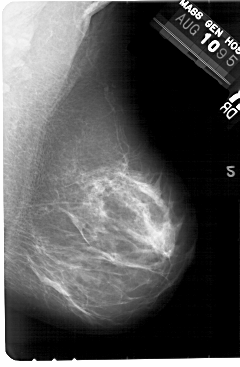

A_1445_1.RIGHT_MLO

RIGHT_MLO LINES 5491 PIXELS_PER_LINE 3586 BITS_PER_PIXEL 12 RESOLUTION 43.5 NON_OVERLAY

FILE: A_1445_1.LEFT_CC.OVERLAY

TOTAL_ABNORMALITIES 1

ABNORMALITY 1

LESION_TYPE MASS SHAPE ROUND MARGINS OBSCURED

ASSESSMENT 3

SUBTLETY 2

PATHOLOGY BENIGN

TOTAL_OUTLINES 1

BOUNDARY